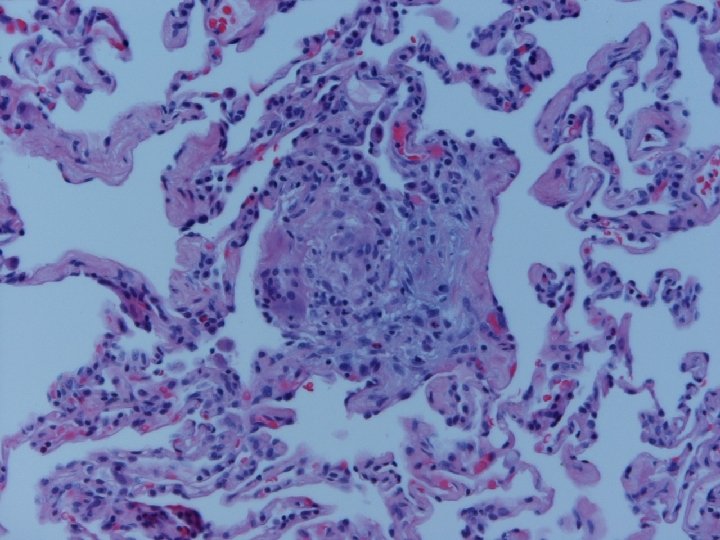

Lung biopsy revealed chronic bronchiolitis/ hypersensitivity pneumonitis (extrinsic allergic alveolitis) with opinion from Mayo Clinic path arriving on 3/30/04. “Hot tub lung due to MAC”. I recommended Prednisone 20 mg. daily, but she had major psychiatric complications for which Seroquel was added and prednisone reduced. X-ray, spirometry, and symptoms resolved. Prednisone tapered and stopped in late May. Recurrence of symptoms and rash in August/September.

Acute HP • Clinical-Abrupt • Lab-ESR, IGG, RA, CRP, LDH, BAL lymphocytosis, restrictive physiology • CXR-micronodular interstitial, but freq. normal-HRCT needed, but not absolute • Histopathology-poorly formed, noncaseating interstitial granulomas, monos, giant cells

Subacute or Intermittent HP • Clinical-gradual cough, dyspnea, fatigue, anorexia, wt. loss, malaise; tachypnea and rales • Lab-BAL lymphocytosis, hypoxemia. Restrictive or mixed spiro, decreased DLCO • CXR-nml, micronodular, reticular. HRCT micronodules, ground glass, emphysema, fibrosis • Histopathology- noncaseating granulomas, bronchiolitis with or w/o organizing pneumonia

Chronic Progressive HP • Clinical-insidious cough, dyspnea, fatigue, weight loss, clubbing • Lab-not very helpful-BAL lymphocytosis but not crisp; restrictive, but usually mixed. DL always reduced, and exertional hypoxemia • CXR-may be normal, but usually progressive fibrosis; emphysema often • Histopathology-granulomatous pneumonia, BO with or w/o OP, fibrosis